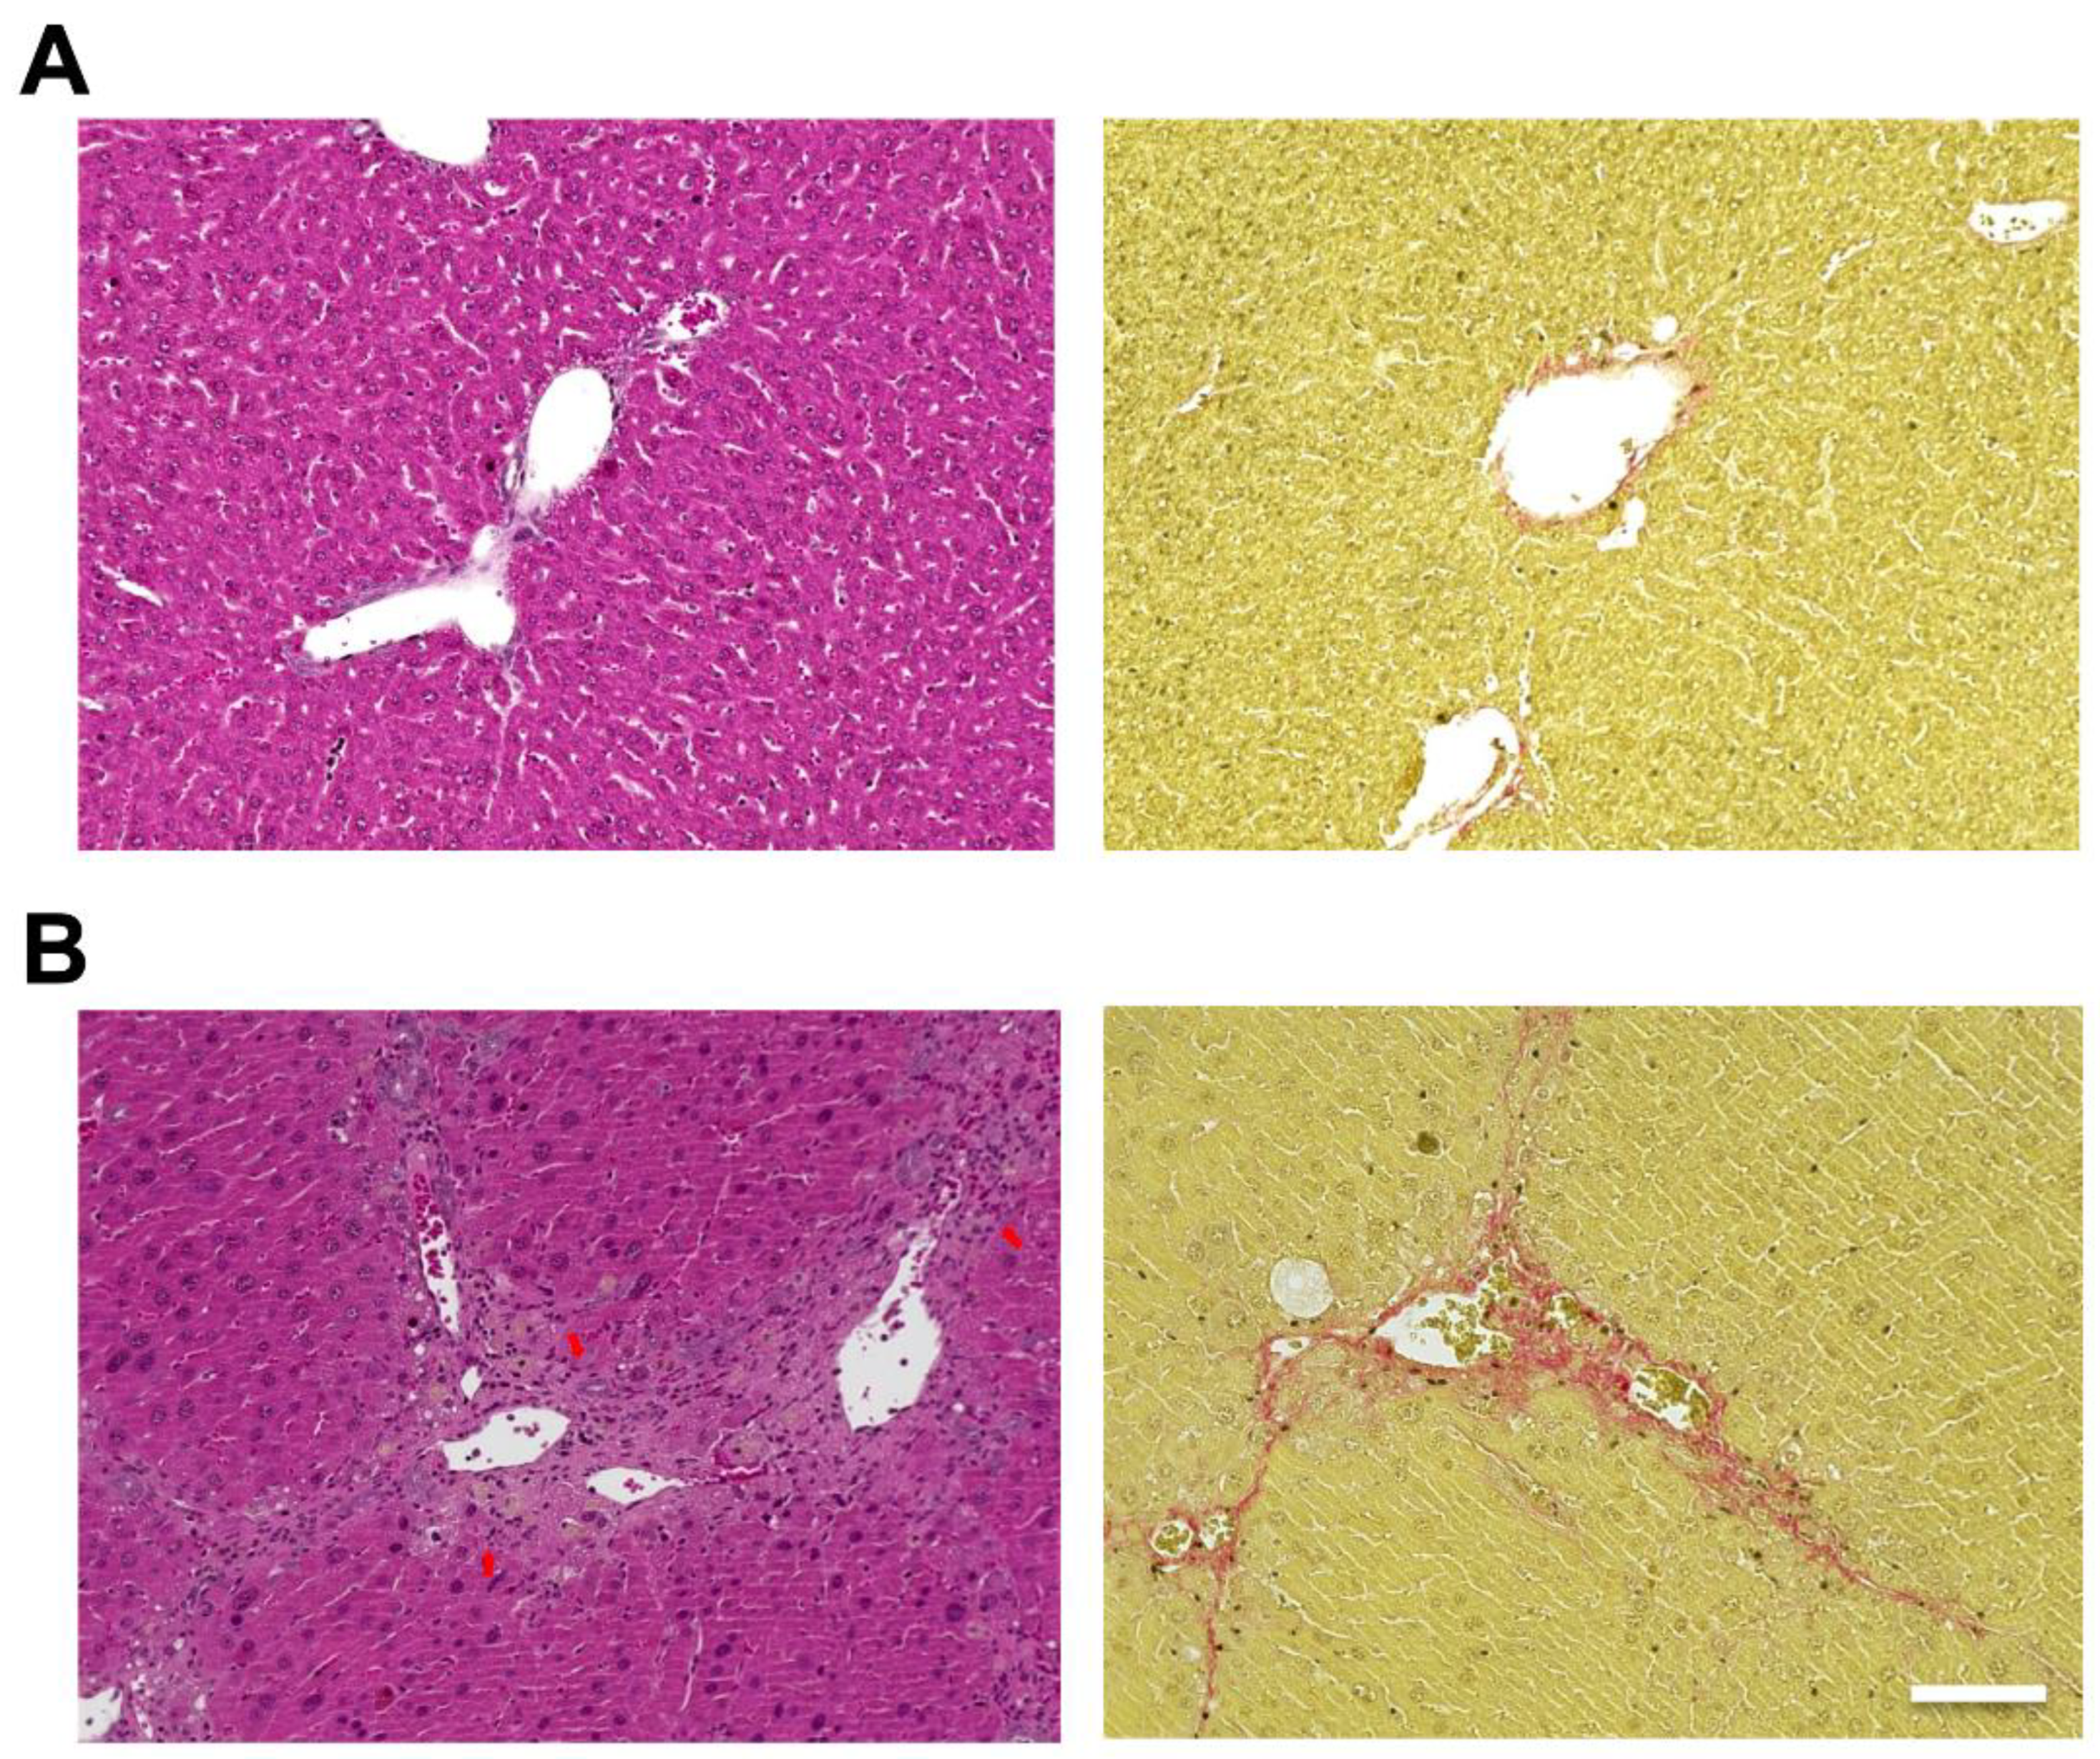

Hematoxylin and eosin (H&E) staining of the liver showed hepatic steatosis and mild hepatocyte ballooning degeneration in WD-fed mice and a significant increase in Non-alcoholic Fatty Liver Disease Activity Score (NAS) [27] (Figure 1). Hepatic tissue from a mouse model of MASH showed about 60% steatosis, moderate inflammatory cell infiltration, and ballooning of hepatocytes (NAS: Steatosis: 2, Inflammation: 2, Ballooning: 1), which are similar to the characteristics of human MASH. Sirius red staining showed mild fibrosis around the portal area. The pathological findings in the liver fibrosis model mice using CCl4 with a control diet showed moderate fibrosis primarily around the portal areas, accompanied by infiltration of inflammatory cells (Figure 2). Fibrosis was more severe in the liver fibrosis model than in the MASH model.

Figure 2.

Carbon tetrachloride (CCl4) induced mouse model, which develops liver fibrosis. Control mice are fed in a control diet (CD) with no administration of CCl4. Hematoxylin and eosin (H&E) staining of livers from (A; left) control and (B; left) CCl4 injected mice. Sirius Red staining of livers from (A; right) control and (B; right) CCl4 injected mice. Scale bar: 100 μm. Arrows: infiltration of inflammatory cells.